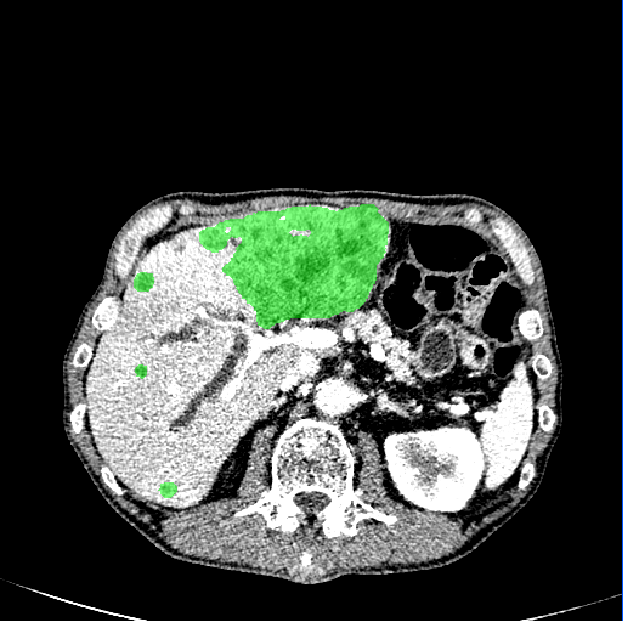

As shown in Fig. 3, our method demonstrates superior qualitative results, especially in the notoriously small tumors segmentation. In Table 1, the results show that the M-Net with the LR-Net achieves better performance than M-Net alone on all the evaluation criteria. This indicates indicates the significance of LR-Net on accuracy improvement. Then, we evaluate the performance of MapDice loss. By comparing the results with and without the MapDice loss, it is apparent that MapDice loss contributes a lot for segmentation accuracy improvement. In particular, the MapDice loss yields the superior results of NI-DM regression, while Dice loss shows a significant drop in the last four columns of Table 1. This indicates that distance map can help the network to capture semantically meaningful regions and produce more accurate reslults. The constant value , used to balance the magnitude difference of two different losses, is also verified to be effective for the performance improvement.